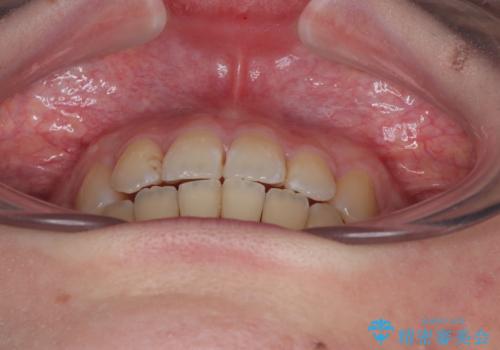

予定の2年半を越えてしまいましたが、無事にきれいな口元に仕上げることができました。

- 上下前歯のデコボコを気にして来院された患者様です。

口元の突出感はあまりなかったものの、デコボコを非抜歯で改善すると出っ歯になる可能性があるため、上下左右の第一小臼歯4本を抜歯し、ワイヤー装置にて矯正治療を行うこととしました。